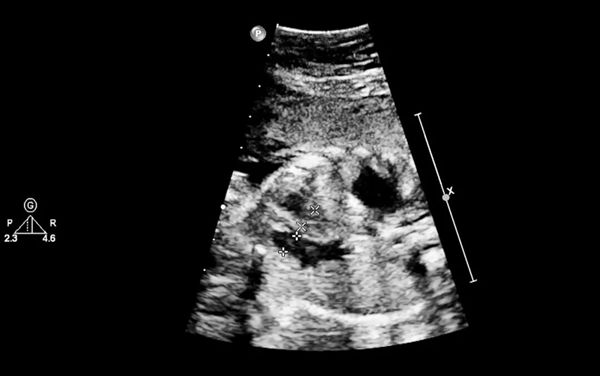

经过精细的调整治疗,移植日到来。张宏展主任准确把握住胚胎的“种植窗”,为林女士移植一枚优质囊胚。还特别叮嘱她,继续保持良好的生活状态,保持轻松愉悦的心情,定期接受规范的检查,这些都有助于预防宫外孕的发生。移植后11天,林女士回院验孕,HCG提示阳性,顺利怀孕。